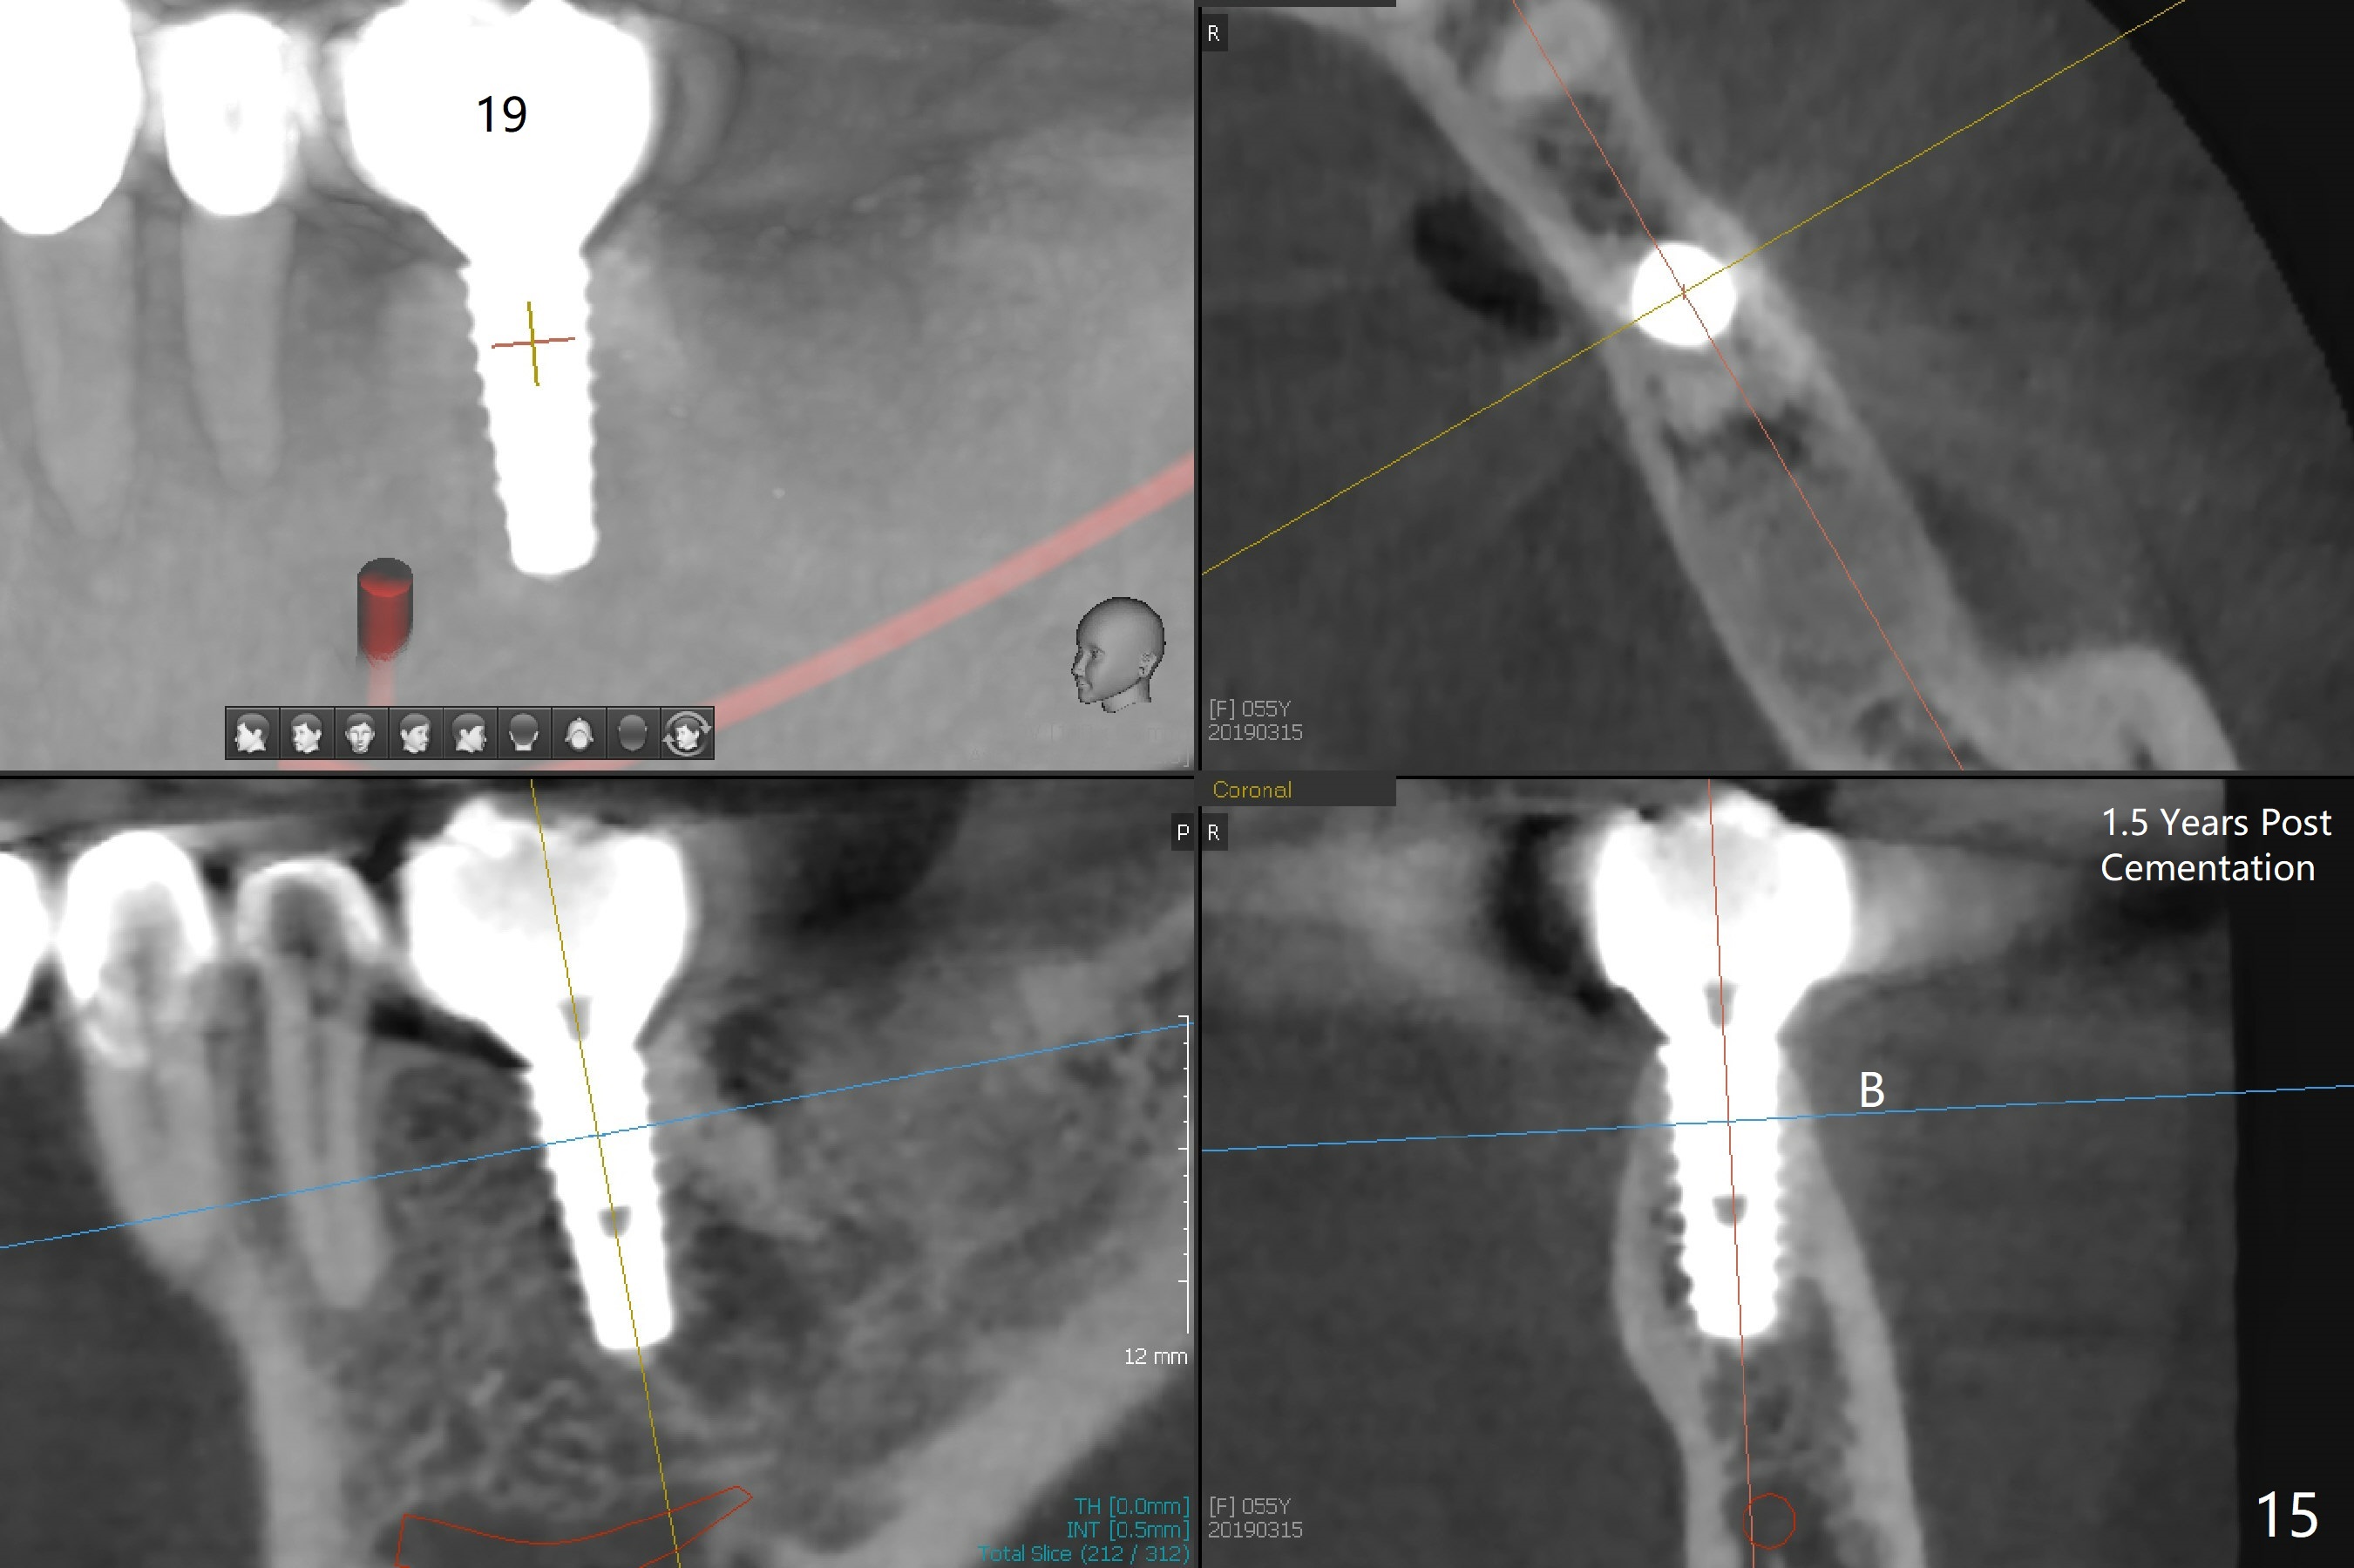

After making a 10 mm incision at the site of #19, #15c blade is used as an osteotome to start bone expansion, followed by Magic Split and Magic Expander (ME, 3 mm in diameter). The depth is approximately the bottom of the mesial socket. The osteotomy beyond the socket has to be done with 1.6 mm pilot drill (Fig.1) in combination of ME. Following ME 4.3 mm and Magic Drill (MD) 3.8 mm for 15 mm (gingival level), a 4.5x11 mm dummy implant is placed with 50 Ncm (Fig.3); the implant looks narrow for the edentulous space. After ME 4.8, MD 4.3 for 13 mm and Final Drill for 15 mm, a 5x11 mm IBS is inserted with >50 Ncm (Fig.3). With 2 more turns of the implant, a 6.5x4(2) mm abutment is placed (Fig.4). Periodontal dressing is applied around the abutment for additional retention. A provisional is fabricated 3 weeks postop. The provisional and abutment are loose 4 months postop (Fig.5). After retightening the abutment, impression is taken for final restoration. There is no bone loss 1 year 3 months post cementation (Fig.6). After use of #100 file (Fig.7), the canal is debrided with #140 file with 1.5 mm shorter in working length with placement of Calcium Hydroxide paste. Pain gets worse post RCT retreatment. There is limited native bone for primary stability when an immediate implant is placed (red dashed line: the superior border of the Inferior Alveolar Canal). Prepare IS regular and extra wide kits and tissue-level implants (>5 mm). Socket preservation may be done instead. If the socket is large and the vein is not so small, prepare PRF. In fact blood drawing fails. When the tooth is extracted, it is sensitive to remove granulation tissue. Socket preservation is done with Vanilla graft at #18 (Fig.8); there is ~3.5 mm bone between the bottom of the single socket and the Inferior Alveolar Canal (red dashed line). The socket at #18 seems to have healed 4 months post extraction (Fig.19), but the bone height appears to have been reduced (compare Fig.10,11). The buccolingual width is also decreased (Fig.12,13). A 4.5 or 5.0x10 mm implant is appropriate for the site (Fig.14). There is no bone loss at #19 (which may be associated with the bone expansion) 1.5 years post cementation (Fig.15). Therefore the osteotomy at #18 will be assisted with bone expanders after 2.2 mm drill.